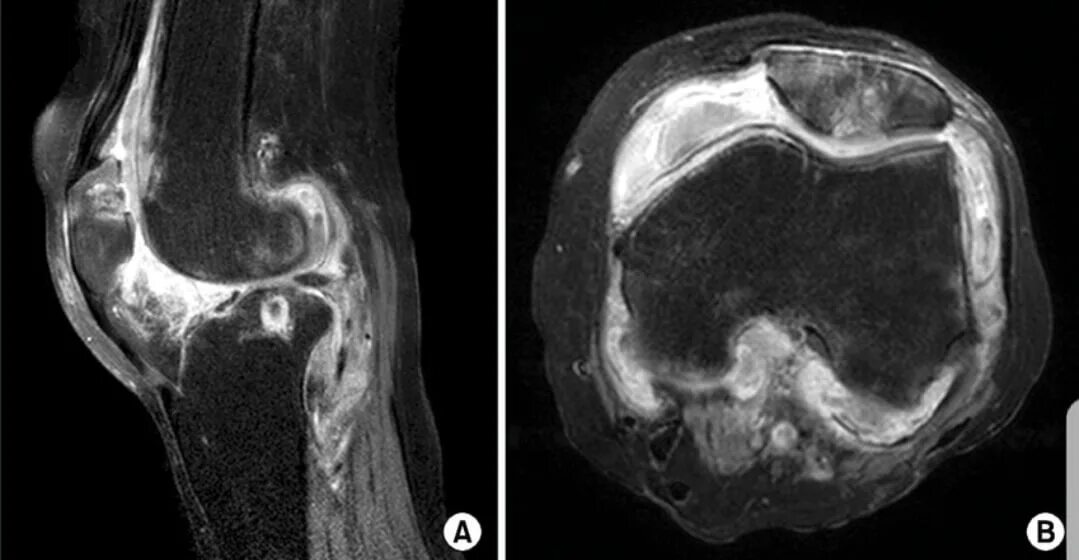

Пигментный виллонодулярный синовит